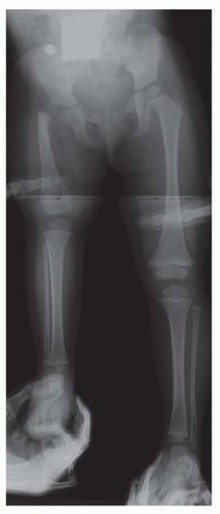

During the initial evaluation of an infant with CFD, pull down supine long AP and lateral view radiographs should be obtained that include the pelvis and both lower extremities. Both lower limbs are “pulled down” to make sure both knees are in maximum extension ( FIG 3 ).

Illustration 7 for Treatment for Congenital Femoral Deficiency: What You Need to Know

FIG 3 • Pull down view long x-ray to assess leg length difference in infancy. Note the hands of the parent.

The supine, long AP view radiograph should be assessed for the overall appearance of the ossific anatomy. This radiograph should allow the physician to classify the type of CFD.

The lengths of both femora and both tibiae should be measured. The difference between them is the LLD, not including the foot. The clinicians should measure from the lateral acetabular edge to the midpoint of the knee joint space for the femoral lengths and from the same midpoint of the knee joint space to the end of the talar ossific nucleus for the tibial lengths. The amount of current LLD can be used with the multiplier method to

predict the overall LLD at maturity.1, 2, 11